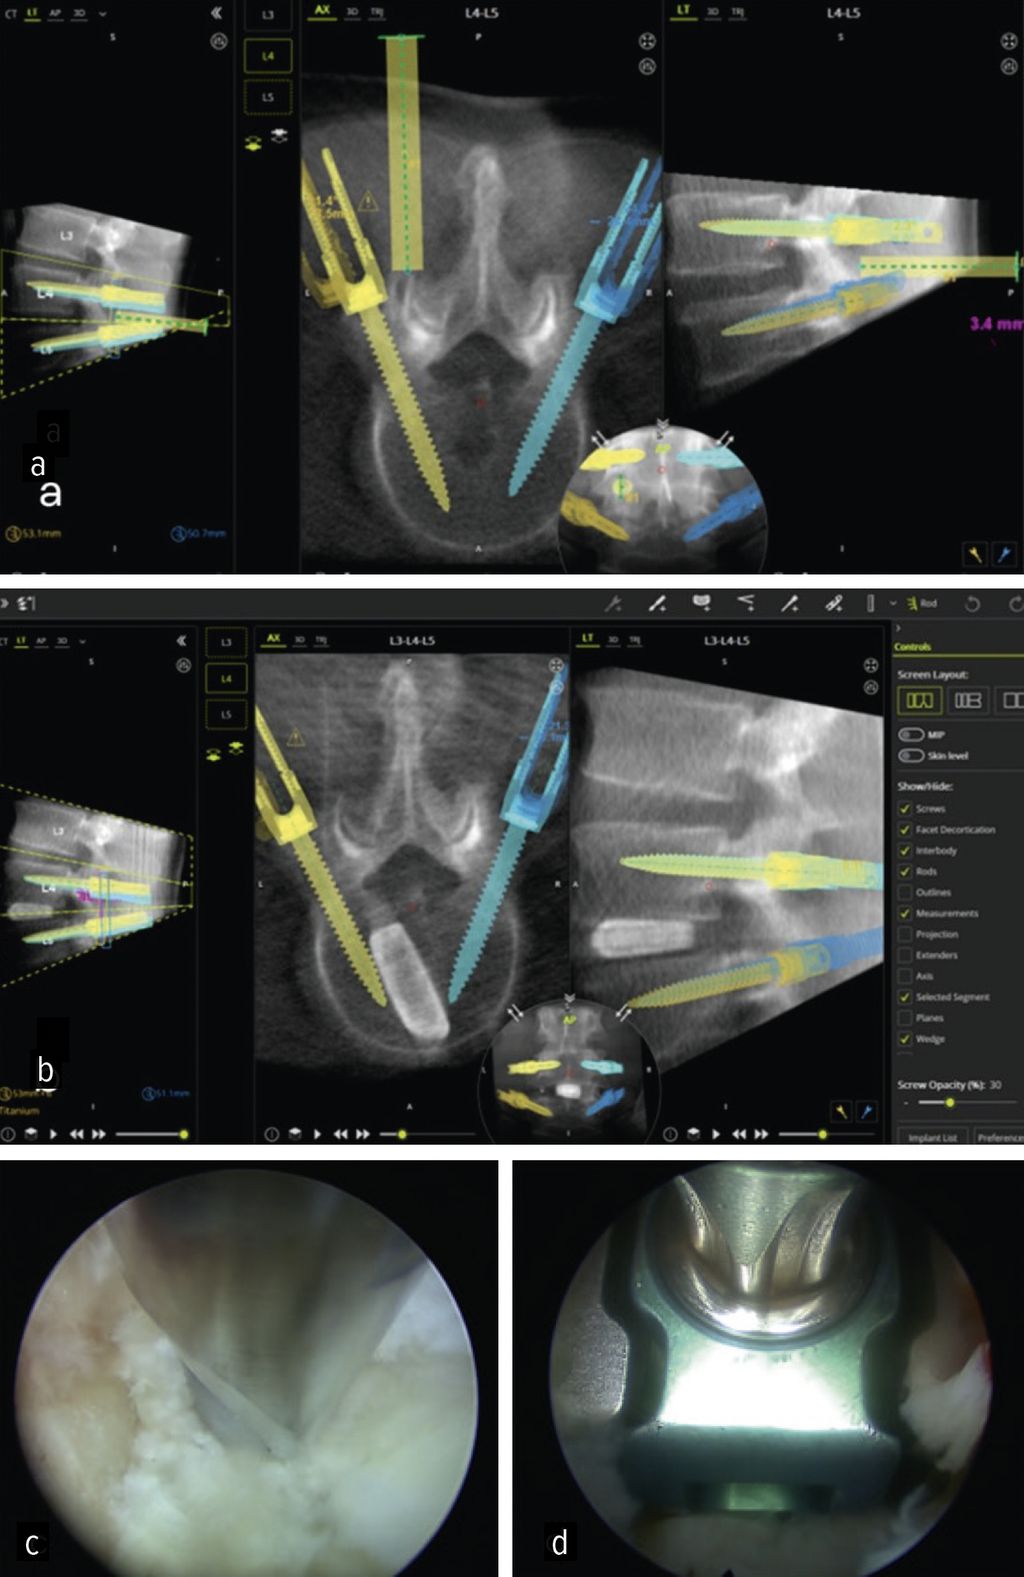

Lumbale interkorporelle Fusion

Die minimalinvasive transforaminale lumbale interkorporelle Fusion (Minimally Invasive Transforaminal Lumbar Interbody Fusion; MIS-TLIF) hat in den letzten Jahren an Bedeutung gewonnen, die aufgrund des geringeren Gewebetraumas mit einer früheren Rekonvaleszenz verbunden ist.24 Aus den gleichen Gründen rückt die endoskopische transforaminäre Interbody Fusion (Endo-TLIF) in den Fokus der Aufmerksamkeit. Endo-TLIF ist eine Erweiterung der MIS-TLIF und erfordert eine unilaterale Resektion des Facettengelenkes. Die Grund- und Deckplattenpräparation gilt als entscheidender Faktor, der die Fusionsrate beeinflusst.24 Die Möglichkeit, unter klarer endoskopischer Sicht die Endplatten präzise darzustellen, erlaubt eine ideale Aufbereitung des Fusionsbettes. Dies könnte zu einer Erhöhung der Fusionsrate beitragen. Zudem profitieren die Patienten durch eine raschere Erholung, einen geringeren Opioidbedarf, eine frühzeitige Mobilisierung und eine verkürzte stationäre Verweildauer.25 Limitationen liegen aktuell bei höhergradigen Listhesen und kollabierten Bandscheibenräumen vor.26 Um das Potenzial der Methodik zu untermauern, bedarf es robuster Studien mit erhöhtem Evidenzlevel sowie eines einheitlichen Standards der endoskopischen Fusionstechniken. Abbildung 6 zeigt eine Planungsanwendung (MazorX® Application, Fa. Medtronic) für Endoskoptrajektorie und Pedikelschraubenimplantation im Rahmen der Endo-TLIF-Operation (a, b). Abbildung b zeigt einen oblique eingebrachten Cage (eFuse® expandable, Fa. Evospine), Abbildung c einen Nukleusresektor (Fa. RIWOspine) bei Präparation des Fusionsbettes. Abbildung d zeigt, dass eine Cagedistraktion unter direkter Sicht möglich ist.